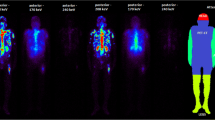

Marrow cavities in spine, pelvis and femur were identified on CT. In order to delineate bone marrow on SPECT slices, regions of interest (ROIs) were drawn on CT slices identifying the marrow tissue. Preserving geometry, the marrow ROIs were then transferred onto corresponding SPECT slices of SPECT/CT scan, allowing uptake quantitation (Figs. 1, 2). The marrow ROIs were divided into three volume of interest (VOI) compartments: spinal marrow, pelvic marrow and femoral marrow. Average counts in each marrow VOI were then converted to activity and activity concentration using calibration factors (see Appendix 1 for a detailed description of calibration of the SPECT/CT scanner). Activity concentration in the bone marrow was then estimated based on activity in the marrow VOIs by correcting for yellow marrow and bone tissue volumes. The correcting factor for yellow marrow volume R was based on ICRP 70 marrow cellularity values and the correcting factor q for bone tissue was based on measurement of CT intensities in marrow VOI (see Appendix 2 for a detailed description of the method).

If haemopoietically active marrow contains CD20-positive cells, uptake in active marrow will be elevated (Fig. 1). This will lead to a radiation absorbed dose deposited in the active marrow which cannot be accounted for by any method currently used in clinical practice. Macey et al. [9] proposed the use of planar imaging of the lumbar spine for quantification. In our extended protocol, we incorporated lumbar spine planar imaging, although it became apparent that this technique was not reliable in our patients. Our SPECT/CT imaging data showed clearly that the majority of NHL patients have para-aortic node involvement (Fig. 2), in which uptake is quite intense, although it may not be demonstrable on planar images. Furthermore even after 5 days there is relatively high activity in major blood vessels (Fig. 2), especially in the aorta, which will be in the field of interest on planar lumbar spine images. Counts from involved lymph nodes and aortic activity cannot be easily differentiated from counts from marrow (Figs.1, 2). Thus planar imaging techniques are unlikely to be reliable for accurate bone marrow uptake quantitation for 131I-rituximab in NHL patients.